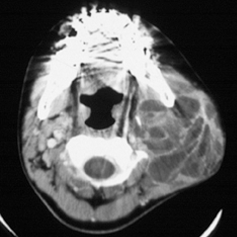

Amazon.co.jp: フルセット 藤田紫乃のふじた式整体科学刻まれた, 診療と研究 | 藤田医科大学医学部 小児外科学講座,